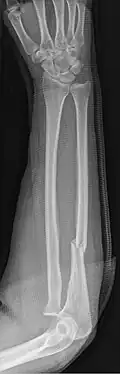

- Monteggia fracture - a fracture of the near to elbow end of the ulna with the dislocation of the head of the radius at the elbow joint.[2]

Monteggia Fracture (fracture of proximal ulna) -